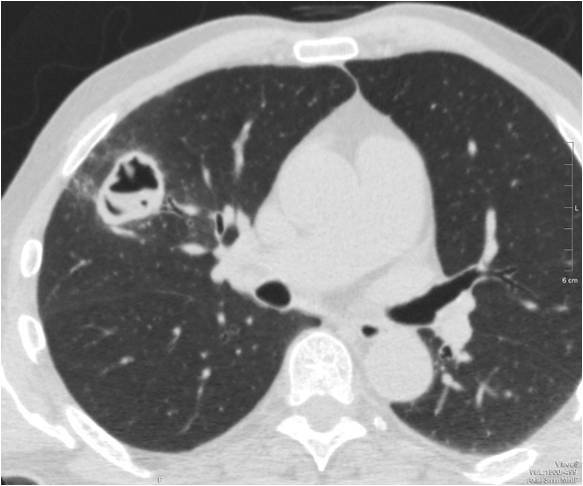

Очаговые изменения

Очаговые изменения в лёгких могут быть разного размера. Очаги мелкого диаметра 1-10 мм выявляются при различных диффузных патологиях лёгочной ткани. Очаги с высокой плотностью и довольно чётки краями в основном наблюдаются в интерстиции лёгкого. Различные очаги низкой плотности, напоминающие матовое стекло, с нечёткими контурами возникают при патологических изменениях в респираторных отделах дыхательных органов.

- Центрилобулярные очаги. Наблюдаются в артериях и бронхах или в непосредственной близости от них. Они могут быть довольно плотными, хорошо очерченными и однородными. Изменения лёгочной ткани такого типа наблюдаются при пневмониях, эндобронхиальном туберкулёзе и разных видах бронхита, преимущественно бактериального происхождения. Есть и другой тип центрилобулярных очагов, в этом случае лёгочная ткань имеет мелкие уплотнения и похожа на матовое стекло.